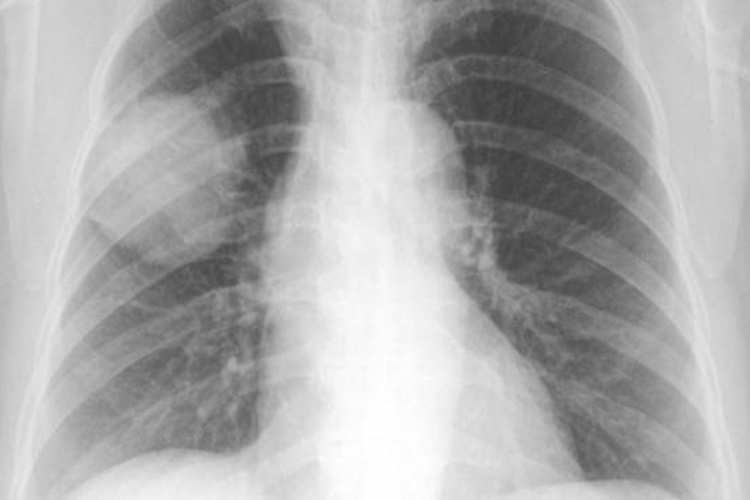

周围型肺癌

周围型肺癌早期多呈局限性小斑片状阴影,边缘不清,密度较淡,也可呈结节、球状、网状阴影或磨玻璃影,易误诊为炎症或结核。中晚期胸片上大多表现为肺内球形肿块影,可见分叶短细毛刺及胸膜凹陷征;当肿瘤坏死经支气管引流后,可形成厚壁偏心空洞;肿块内钙化较少见。